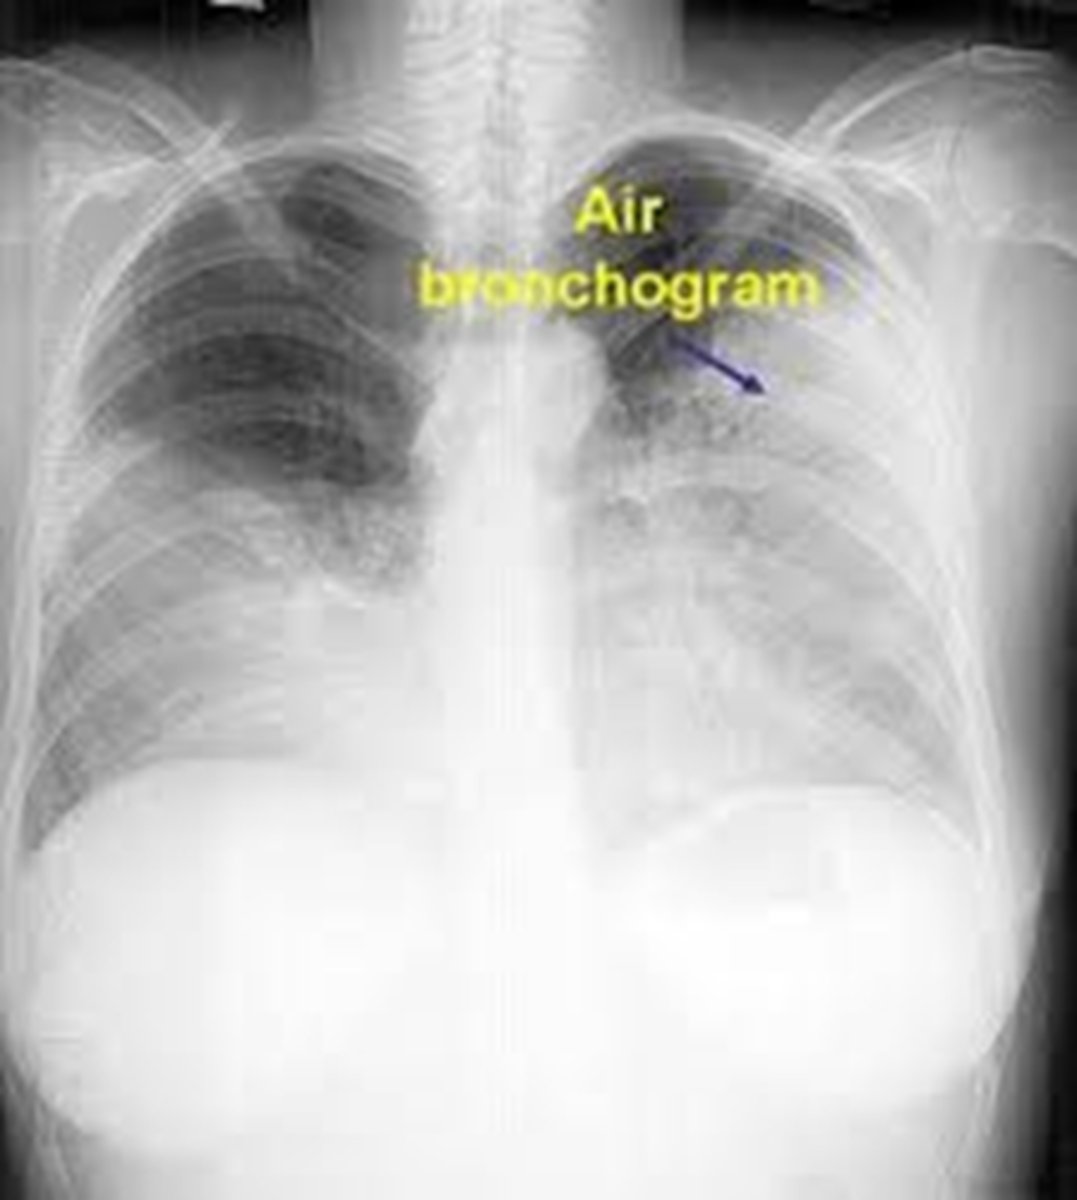

PNA (pneumonia)

What is happening in the right lower lobe?